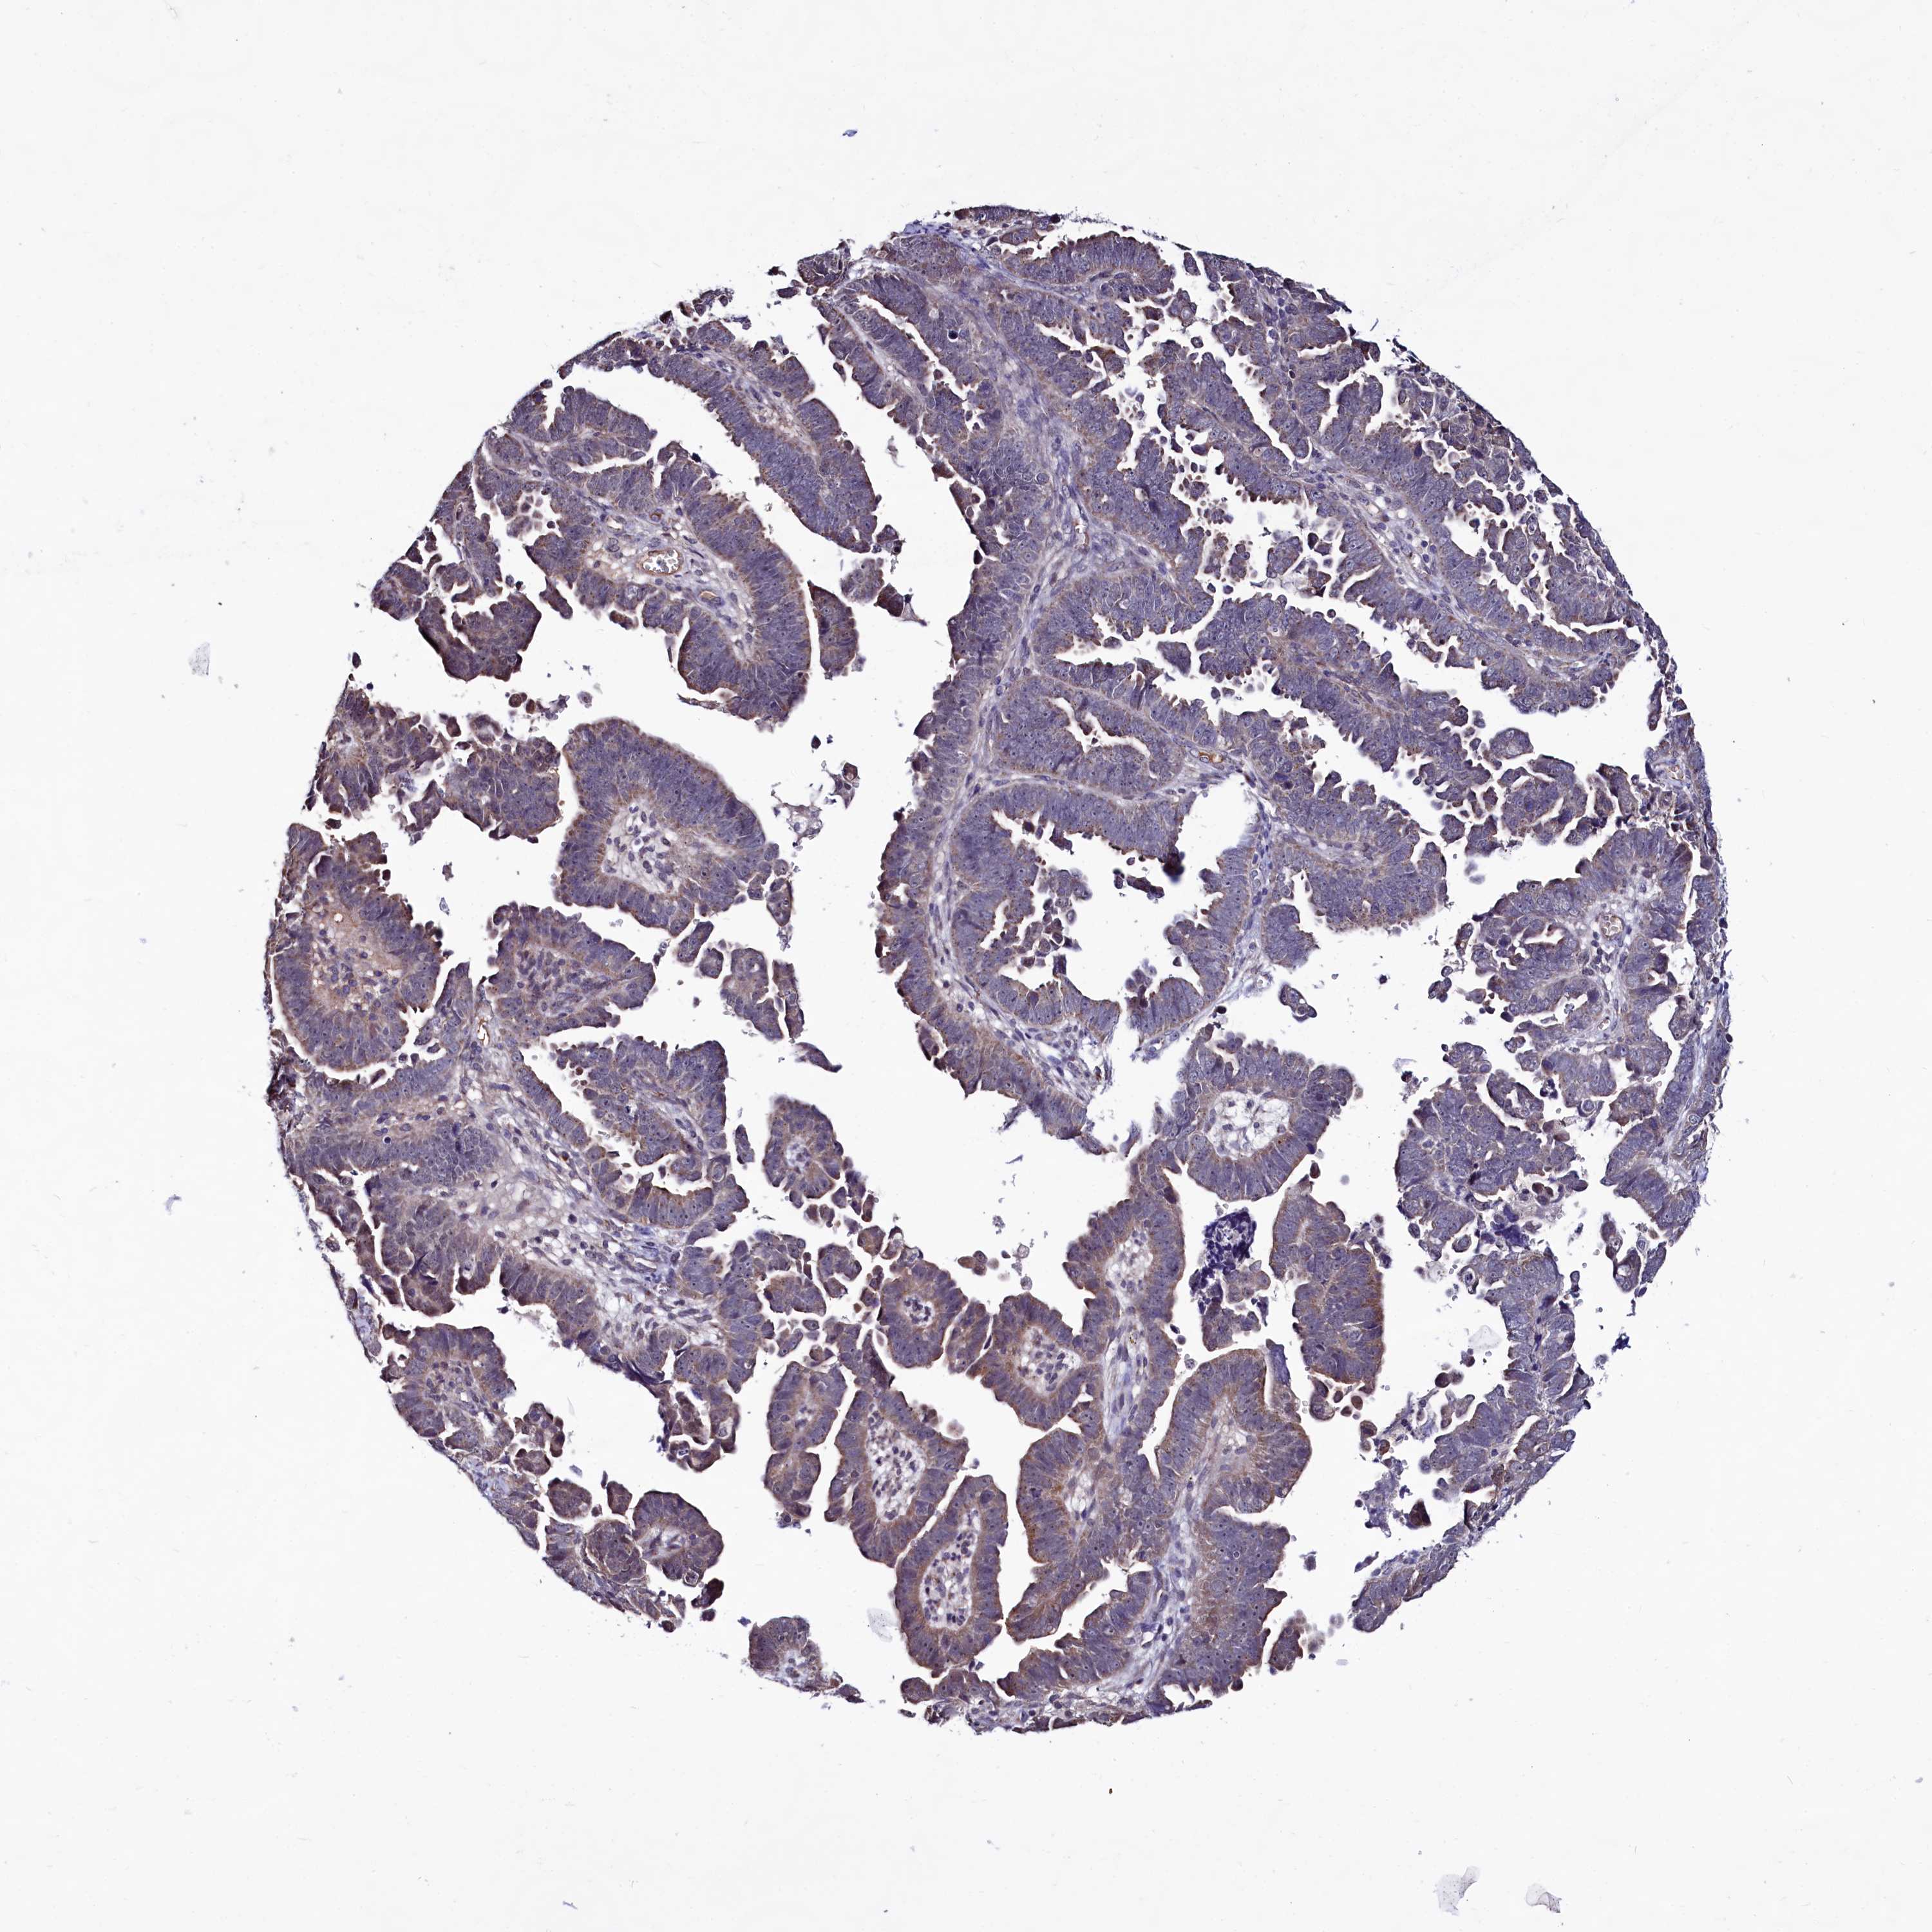

ENDOMETRIAL CANCER - Protein expressioni

A mouse-over function shows sample information and annotation data. Click on an image to view it in a full screen mode. Samples can be filtered based on level of antibody staining by selecting one or several of the following categories: high, medium, low and not detected. The assay and annotation is described here.

Note that samples used for immunohistochemistry by the Human Protein Atlas do not correspond to samples in the TCGA dataset.

Antibody stainingi

Antibody staining in the annotated cell types in the current human tissue is reported as not detected, low, medium, or high, based on conventional immunohistochemistry profiling in selected tissues. This score is based on the combination of the staining intensity and fraction of stained cells.

Each image is clickable and will lead to virtual microscopy that enables deeper exploration of all samples and also displays staining intensity scores, fraction scores and subcellular localization as well as patient and tissue information for each sample.

Antibody HPA040196

Antibody HPA040213

Staining

High

Medium

Low

Not detected

Intensity

Strong

Moderate

Weak

Negative

Quantity

>75%

75%-25%

<25%

None

Location

Nuclear

Cytoplasmic/membranous

Cytoplasmic/membranous,nuclear

Adenocarcinoma, NOS

Adenocarcinoma, metastatic, NOS